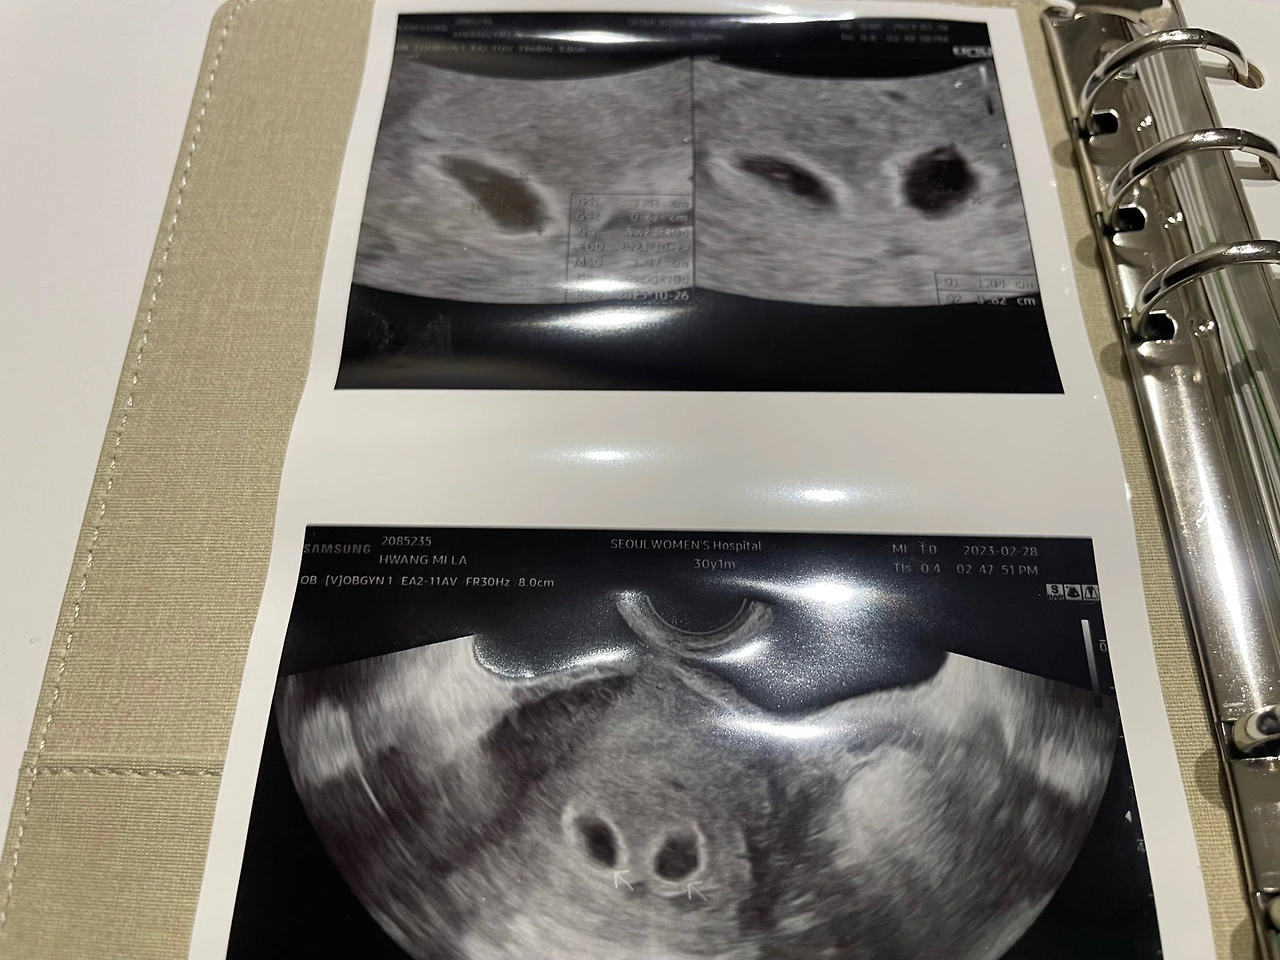

드디어 우리 차례가 되었다. 이제 결과를 확인할 시간이 된 것이다. 간단한 인사말과 소개를 마치고 초음파 진료를 위해 아내는 자리를 옮겼다. 남편은 잠시 후에 그 공간에 함께 할 수 있는데, 그리 오래 걸리지는 않는 시간이다. 초음파 진료 준비를 마치고, 의사 선생님이 오셔서 의료 기기로 아내의 배를 살펴보기 시작했다. 투명한 젤을 아내의 배 주위에 바르고는 기기를 갖다 대었다.

[임신 맞네요, 아기집이 있네요, 축하드립니다.]

처음부터 무척이나 상냥했던 담당 선생님의 진심 어린 축하의 인사를 건네 듣고 우리 부부는 그제야 긴장이 풀렸다. 5년이라는 시간을 기다린 끝에 드디어 우리 부부에게도 아가들이 찾아왔다는 것을 실감하는 순간이었다. 고생했다고, 그동안 힘들었지만 잘 버텨주었다고 우리 부부는 서로를 향해 눈빛으로 위로를 건넸다. 기다렸던 순간이 현실이 된 순간, 우리는 벅차오르는 감정을 주체하지 못했다. 그 순간.

[응? 잠시만요, 혹시 시험관 하셨어요?]

임신을 확인하고 검사를 마치는 줄 알았는데, 의사 선생님의 손놀림은 멈추지 않고 우리를 향해 물으셨다. 시험관이라는 단어가 나오자 순간적으로 우리 부부는 긴장했다. 5년 동안 임신이 되지 않아 걱정과 스트레스는 있었지만 시험관 까지는 생각하지 않았었다. 앞으로도 마찬가지였다. 순리대로. 찾아오면 찾아오는 대로, 찾아오지 않으면 찾아오지 않는 대로 살아갈 참이었다. 그래서였나 의사 선생님의 질문에 꽤나 불안한 마음이 들었다.

[아니요? 왜요, 선생님? 무슨 일이.. 있는 건가요?]

아내의 손을 꼭 잡으며 눈빛으로, '별일 없을 거야'라는 신호를 보내며 고개를 두 번 끄덕였다. 그리고 전혀 예상치도 못한 선생님의 말이 이어졌다.

[허허, 이거 아기집이 하나 더 있네요? 축하해요~ 쌍둥입니다.]

KakaoTalk_Photo_2023-10-23-21-15-50.jpeg 쌍둥이들이 찾아올 줄은... 정말 몰랐습니다 :)